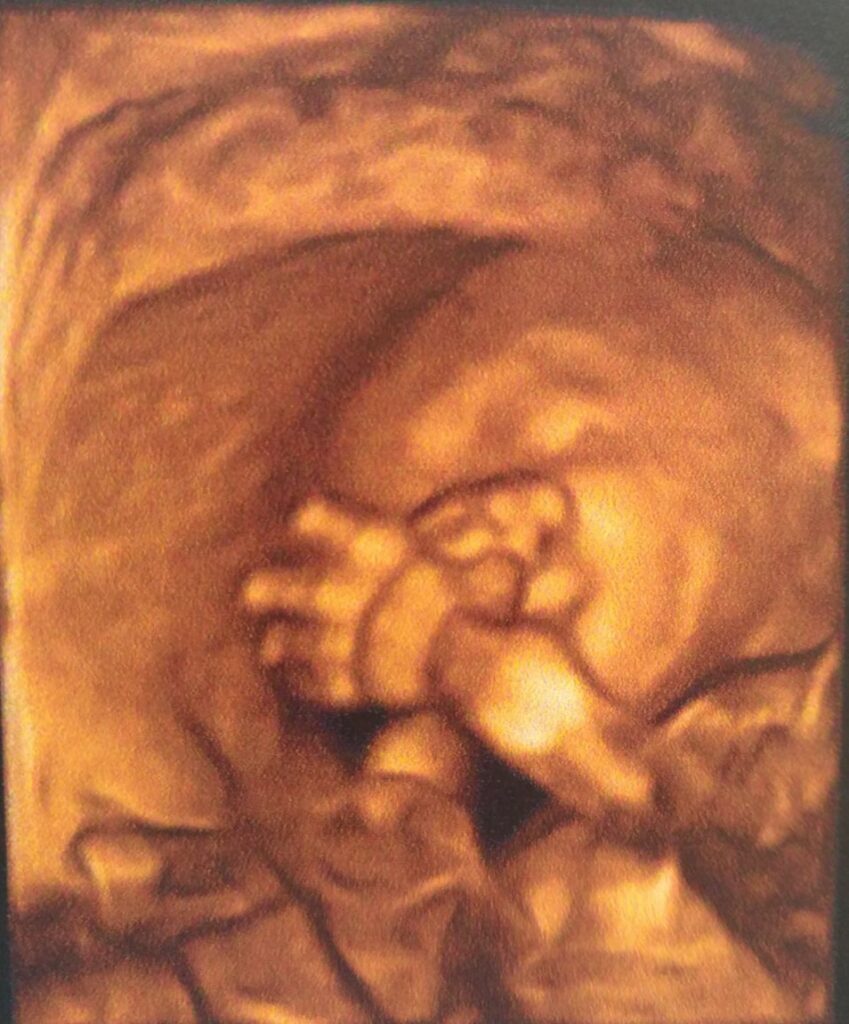

- Bébés nés après des stress prénataux ou naissance compliquée (forceps, césarienne, cordon autour du cou, en siège, souffrance fœtale…)

La période de la conception et de la grossesse est fondatrice. En séance, nous pouvons :

- Apaiser les stress liés à un parcours PMA ou à une grossesse à risque

- Libérer les émotions anciennes ou héritées qui peuvent freiner l’accueil du bébé

- Accompagner les peurs, les douleurs, les transformations du corps

- Préparer un lien d’attachement sécurisant entre parent et bébé

- Se reconnecter à son ressenti corporel, à sa féminité, à la vie qui grandit

- Créer un lien fort et sécure avec le bébé in utéro

La grossesse est une période de grande plasticité émotionnelle. Ce que vit la mère est ressenti par le bébé.